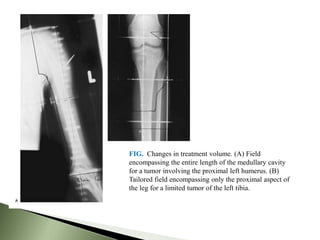

FIG. Changes in treatment volume. (A) Field

encompassing the entire length of the medullary cavity

for a tumor involving the proximal left humerus. (B)

Tailored field encompassing only the proximal aspect of

the leg for a limited tumor of the left tibia.

FIG. Changes intreatment volume. (A) Field encompassing the entire length of the medullary cavity for a tumor involving the proximal left humerus. (B) Tailored field encompassing only the proximal aspect of the leg for a limited tumor of the left tibia.